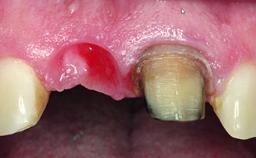

A 63-year-old male patient was referred for a consultation and treatment of partial edentulism in the maxilla. The patient presented with residual anterior teeth and declined a partial removable prosthesis. He reported that the maxillary posterior teeth had been extracted due to mobility and periodontal disease two months before the consultation. The patient’s chief complaint was that his residual maxillary teeth were mobile and that he was unable to chew. The patient’s desire was a stable and comfortable fixed maxillary rehabilitation. The patient was a light smoker (fewer than 10 cigarettes/ day), and his medical history was without significant findings. He was not on any regular medication at the time of consultation. The extraoral examination revealed a normal physiognomy with a correct distribution of the facial thirds. The patient presented a low lip line, and the transition line between teeth and soft tissues was not exposed during a forced smile.